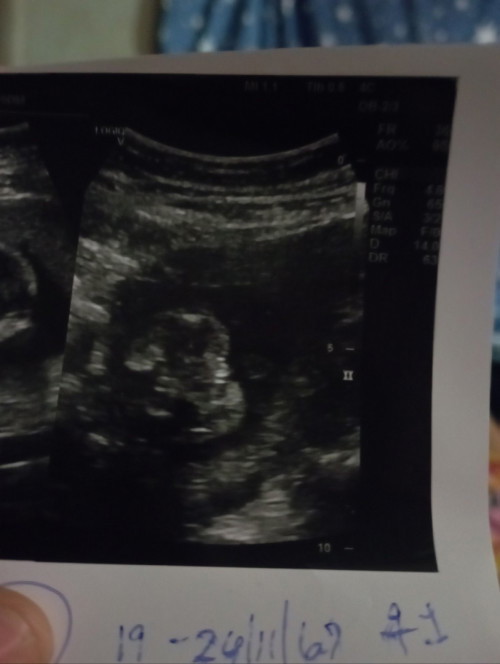

ไปซาวด์มาอายุครรภ์ 17w5d คุณหมอสันนิฐานว่าอาจจะเป็นผู้ชายหรืออาจจะสายสะดือ อยากสอบถามแม่ๆว่า อายุครรภ์เท่าไหร่ถึงจะชัวร์เพศคะ แม่อยากได้ลูกสาว🥹🤍#ท้องแรก

อายุครรภ์เท่ากันกันเลย ซาวด์ล่าสุด หมอแจ้งสายสะดือบัง